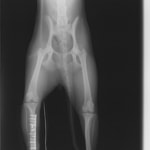

ペルシャ猫 11ヶ月齢 雄

他院にて左大腿骨遠位の成長板骨折(salter-harrisⅠ型)が認められており、治療相談を目的として来院。当院にて、キルシュナーワイヤーを用いたピンニングにより骨折部位の整復を行いました。術後の経過は良好で、現在も経過観察中です。

術前レントゲン

術後レントゲン